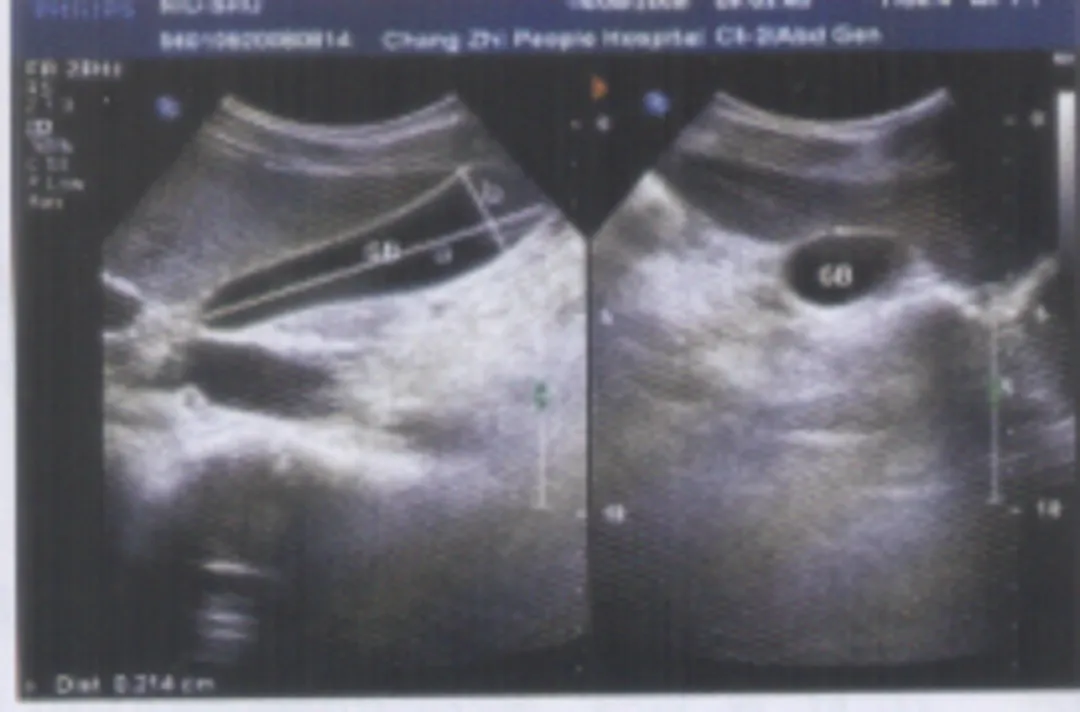

充填型胆囊结石

● 胆囊内胆汁较少或无胆汁,胆囊腔的无回声区消失,胆囊无正常的轮廓或形态,声像图仅表现为胆囊前壁呈弧形或半月状的强回声带,后方伴较宽声影,致使胆囊后壁不显示。

● 囊壁结石声影三联征(WES征:wall-echo-shadow征):前方为增厚胆囊壁的弱回声包绕中间结石的强回声,后方伴有声影。